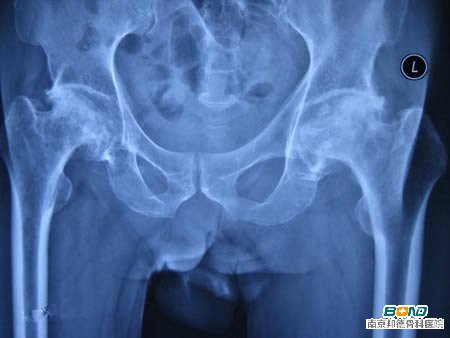

1、股骨头坏死

股骨头坏死至发现至今,已从过往的少见病转变为多发病、常见病。30至60岁是此病发作的高峰期。股骨头坏死常见的症状就是疼痛,且疼痛部位多集中于髋关节、大腿近侧,可放射至膝部。疼痛既可表现为持续痛,也能是静息痛的形式。当然,除了髋关节等部位疼痛之外,也会存在髋部活动受限,特别是旋转活动受限,或有痛性和短缩性跛行。【股骨头坏死的治疗方法】

2、髋关节炎

髋关节承受着人体巨大的重量,由于肥胖、骨质疏松、外伤等原因导致髋关节软骨变形、受损、退变等,导致特征性病变。一般而言,髋关节炎的主要表现为臀外侧、腹股沟等部位疼痛,可放射至膝盖。包括髋关节疼痛、肿胀、内部积水、软骨磨损、骨刺增生、关节变形等等。【关节炎如何治疗?】